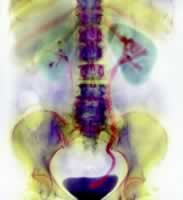

药物治疗解除泌尿道结石梗阻已有报告,但这并不是普遍使用的方法。假如这些治疗方法有效,将会增加泌尿道结石的治疗选择。美国Hollingsworth等的一项荟萃研究表明,药物治疗(钙离子通道阻滞剂或α受体拮抗剂)可促使泌尿道结石排出,可使得许多泌尿道结石患者不需行手术治疗。[Lancet 2006,368(9542): 1171]

研究者检索了截至2005年7月份的相关文献,那些使用钙离子通道阻滞剂或α受体拮抗剂的随机对照研究被纳入分析,最终对9项临床试验的资料(患者总数共693例)进行了汇总分析。主要转归指标为排出结石的患者比例。

结果表明,使用钙离子通道阻滞剂或α受体拮抗剂的患者较未使用的患者结石排出的可能性高65%(汇总危险比α受体拮抗剂为1.54,钙离子通道阻滞剂加类固醇类药物为1.9)。

研究提示:虽然有必要进行一项高质量的随机临床试验去证实药物治疗的疗效,但此研究表明药物治疗方法(钙离子通道阻滞剂或α受体拮抗剂)可促使泌尿道结石排出,从而使患者避免手术治疗。

Hollingsworth等的汇总分析证实了一种紧急处理输尿管结石的方法,对于那些尿结石直径<1 cm,特别是那些结石位于远侧输尿管的接受观察的患者,应该值得尝试药物排石治疗。, 百拇医药